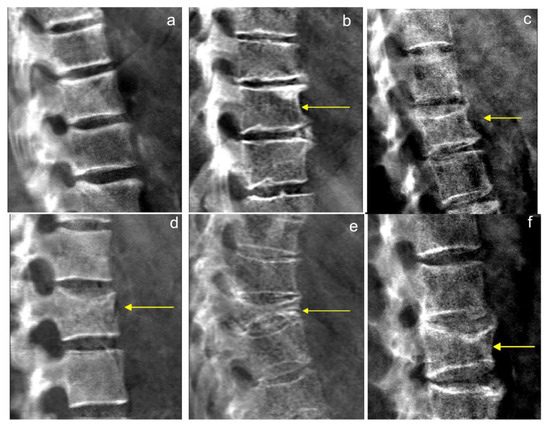

2.3. DXA-VFA Image Annotation

3.2. Point-Wise Landmark Annotation Accuracy

3.3. Image-Wise Annotation Accuracy